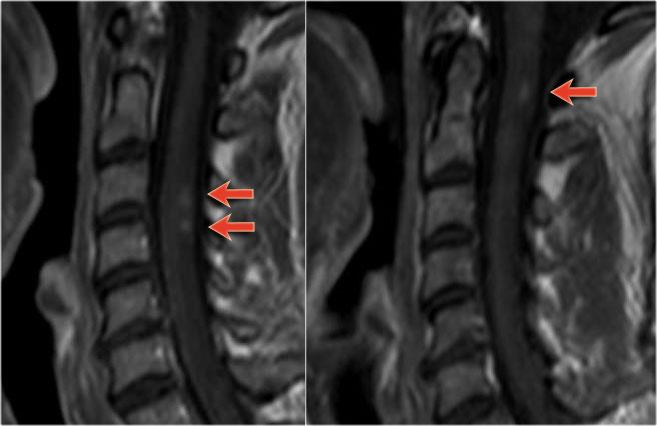

Bên trái là hình ảnh của bệnh nhân nam 60 tuổi mắc u tế bào hình sao.

Bệnh nhân nhập viện với đau vùng ngực và rối loạn cảm giác chi dưới trái, tiếp theo là liệt nửa người trái.

Có tăng tín hiệu đa đoạn trên chuỗi xung T2W kèm phù nề nhẹ, tương tự như hình ảnh đã thấy trong các trường hợp TM.

Trên CE-T1W có vùng ngấm thuốc tương phản từ.

Vùng ngấm thuốc có hình thái nghiêng về u hơn, nhưng việc phân biệt vẫn còn khó khăn.

Hình bên trái là u tế bào hình sao ở bệnh nhân 66 tuổi, nhập viện vì các triệu chứng cảm giác tiến triển dần.

Sinh thiết xác nhận chẩn đoán u tế bào hình sao.

Tiếp tục theo dõi hình ảnh tái khám.

Bệnh nhân không có chỉ định phẫu thuật và hình ảnh tái khám cho thấy bệnh tiến triển.